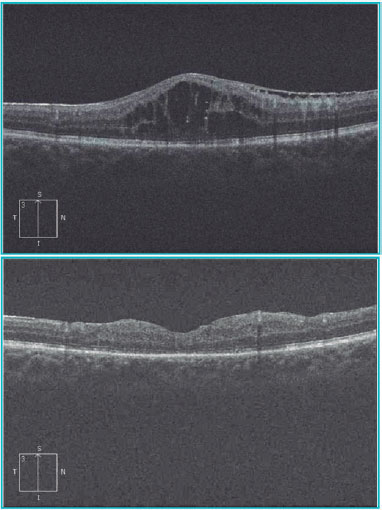

The patient was stable, his legion remained unchanged, and his IOP was controlled after surgery. The patient’s visual acuity improved to 20/70 (0.54 logMAR), and we determined that his low visual acuity was caused by the epiretinal membrane and not by the fistula. Figure 4 shows the OCT pre- and postsurgical treatment.

02-fig04.jpg)